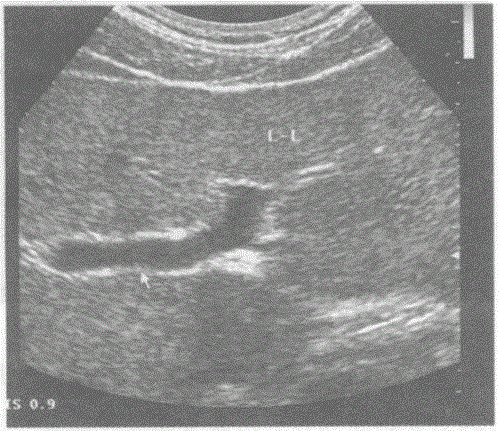

问题 下图是肝脏横切正常超声图像,请回答箭头所指部位的解剖名称:

选项 A.门静脉左支横部 B.门静脉左支矢状部 C.门静脉左内支 D.门静脉左外下支

答案 A